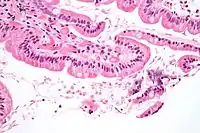

Ґрунтується на методі мікроскопічного дослідження — прямої паразитоскопії, виявленні цист у свіжому калі та вегетативних форм (трофозоїти) лямблій у дуоденальному вмісті. При проносі в калі можуть виявлятися трофозоїти. Пошук паразитів у калі бажано здійснювати не менше 3 разів з проміжками 1-2 дні. Цисти лямблій при тяжкій інвазії можна знайти й у зіскрібках з поверхні язика. Частота знахідок збільшується при проведенні повторних досліджень, а також попередньої підготовки (прийом жовчогінних препаратів 5-7 днів до обстеження), використанні методів формалін-ефірного збагачення, реакції імунофлюоресценції (РІФ) і люмінесцентної мікроскопії за допомогою акридинового оранжевого. У випорожненнях можна також виявити антигени лямблій методами зустрічного імуноелектрофорезу.